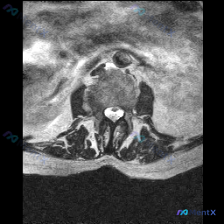

收到一份腰椎MRI T2轴位单层影像,问题是评估椎间盘病变,我整理了完整分析思路和大家分享。

这是腰椎层面的轴位T2序列图像,先给大家整理观察到的客观表现:

- 骨性结构:椎体骨髓信号均匀,双侧关节突关节形态对称,间隙清晰,没有明显骨赘、硬化,椎体后缘也没有骨质增生

- 椎间盘:中心髓核T2信号略有减低,提示轻度脱水退变;椎间盘后缘形态完整,没有局限性向后突出/脱出,也没有对称性膨出,后缘基本和椎体后缘轮廓一致

- 椎管与神经:硬膜囊形态正常,没有受压变形,前方硬膜外脂肪间隙清晰,侧隐窝形态好,神经根出口没有占位压迫,黄韧带没有肥厚内聚,中央椎管和侧隐窝都没有狭窄

- 其他:椎旁肌肉形态信号正常,没有萎缩脂肪浸润,没有看到滑脱、骨折、肿瘤、感染的征象